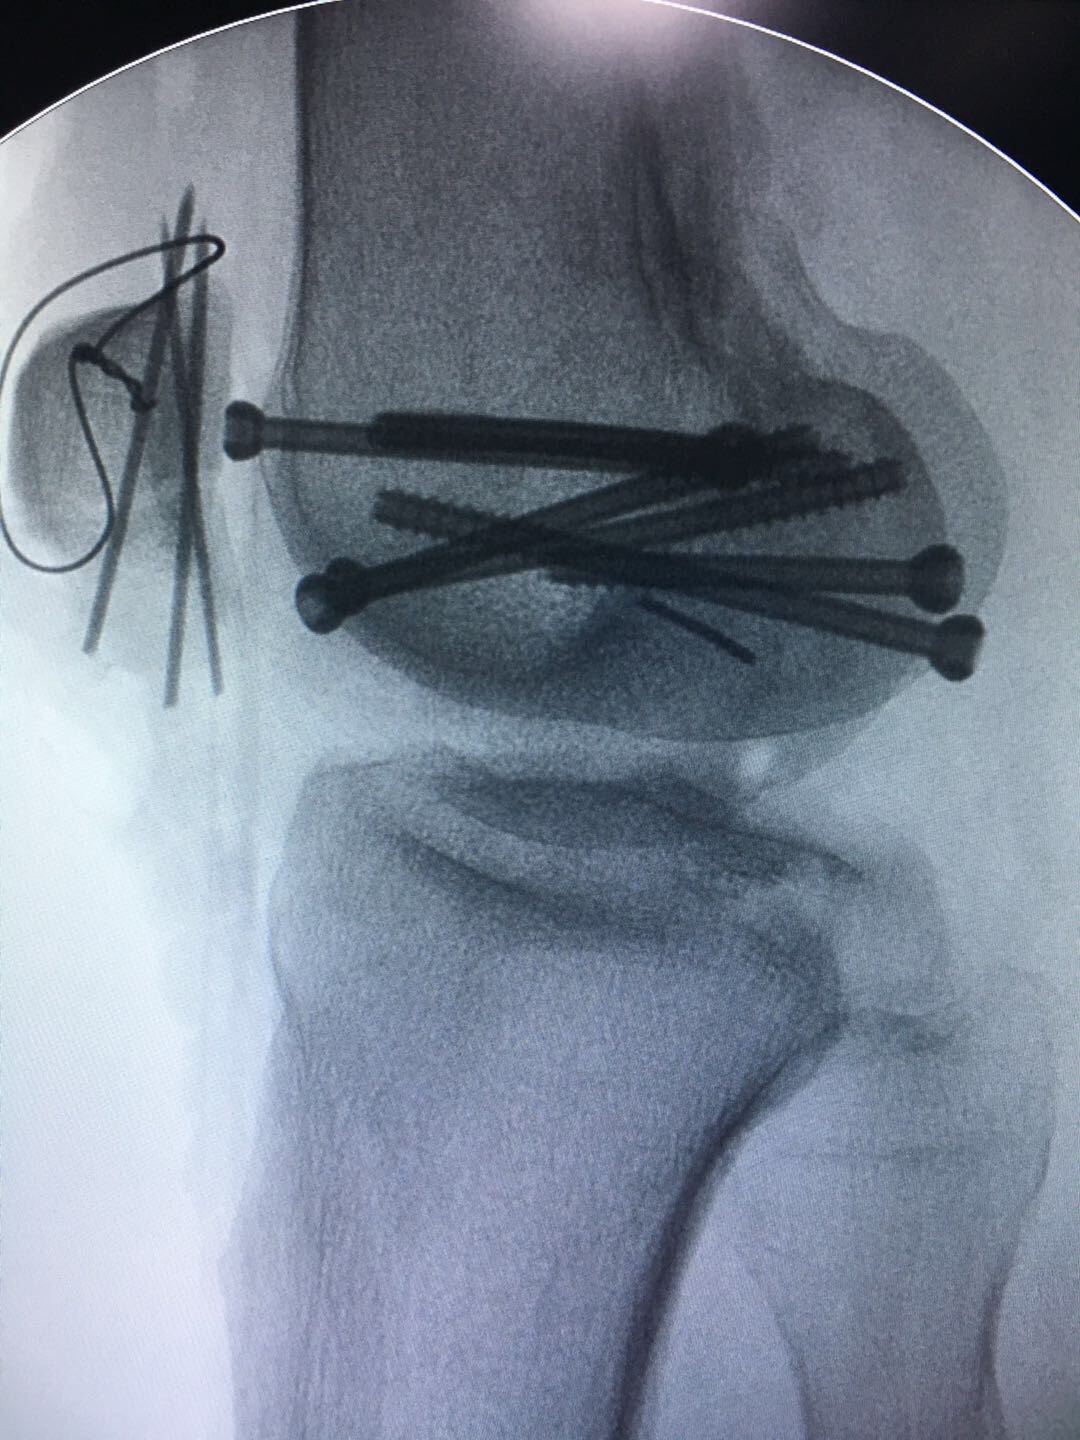

最近一例hoffa骨折手术

图片尺寸1920x1080